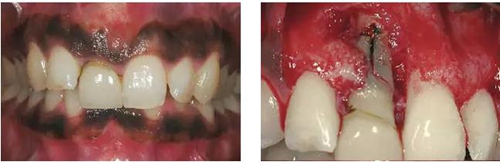

圖1、該病例顯示了厚齦生物型和中弧線形齦乳頭形態(tài)。右上中切牙由于牙根縱裂而需要拔除。由于該患牙伸長(zhǎng),使得軟組織量垂直向增加。牙齦色素沉著是個(gè)美學(xué)挑戰(zhàn)。

圖2、翻開(kāi)全厚瓣可見(jiàn)明顯的牙根縱裂,唇側(cè)骨板2/3受到累及而缺損。